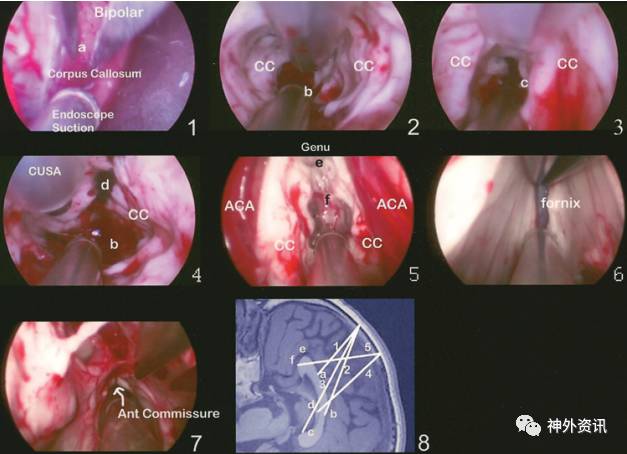

使用双极电凝切开胼胝体表面(图2),在中线处用超声吸引器吸除胼胝体组织。向前从大脑前动脉A2段至胼胝体膝部,确定透明隔腔。继续分离,至胼胝体嘴部。向后至胼胝体压部,再分开中间帆隔膜,显示脉络丛。

图2. 内镜下胼胝体切开术。图1-5所示的手术过程,按图8 MRI矢状位上示意的切口方向进行;图6和图7分别显示切开穹隆和前联合。CC:胼胝体。